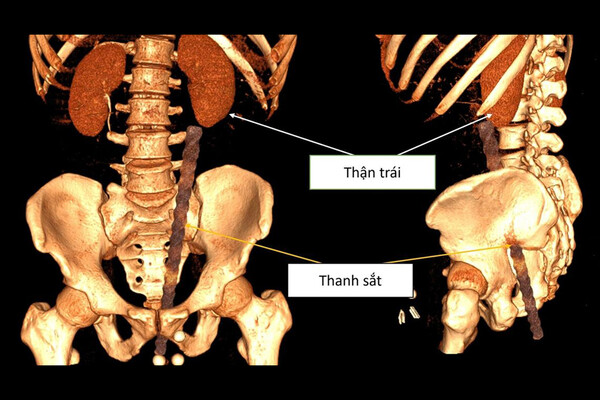

Обследование показало, что арматура вошла через анальное отверстие мужчины и повредила несколько внутренних органов. По данным врачей, металлический прут вызвал сильное кровотечение в анальном канале, мочевом пузыре и брюшной полости. Также были зафиксированы повреждения органов таза.

Во время операции медики обнаружили, что объект находится опасно близко к поясничной области пациента. У мужчины диагностировали ушиб передней стенки прямой кишки длиной около 3 см, повреждение левого мочеточника, разрыв возле почечной лоханки, а также разрыв стенки левой подвздошной артерии, что привело к сильному внутреннему кровотечению и образованию крупной гематомы.